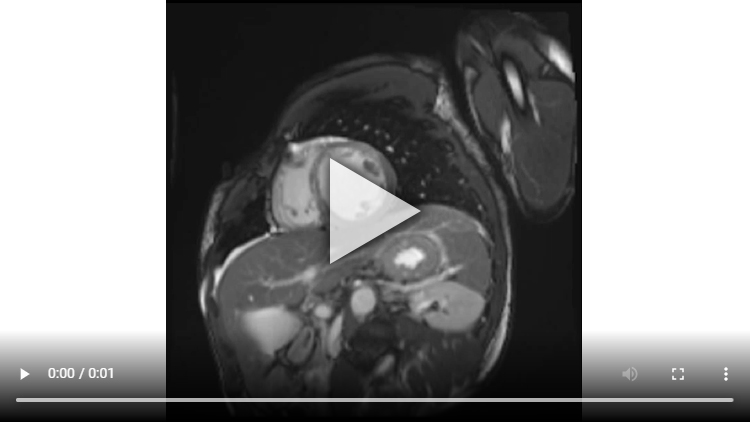

Figure 1A : Séquence Ciné-IRM - Coupes petit-axe médian

Présence d’un VG dilaté avec VTD VG mesuré à 119 ml/m2 associé à une large hypokinésie sévère, voire akinésie dans certains segments, de toute la paroi antéro-septo-apicale et débordant sur la paroi apico-latérale.

Altération de la FEVG mesurée à 33% après segmentation VG.

Aucun thrombus intra-VG n’est visualisé sur ces séquences de ciné-IRM.